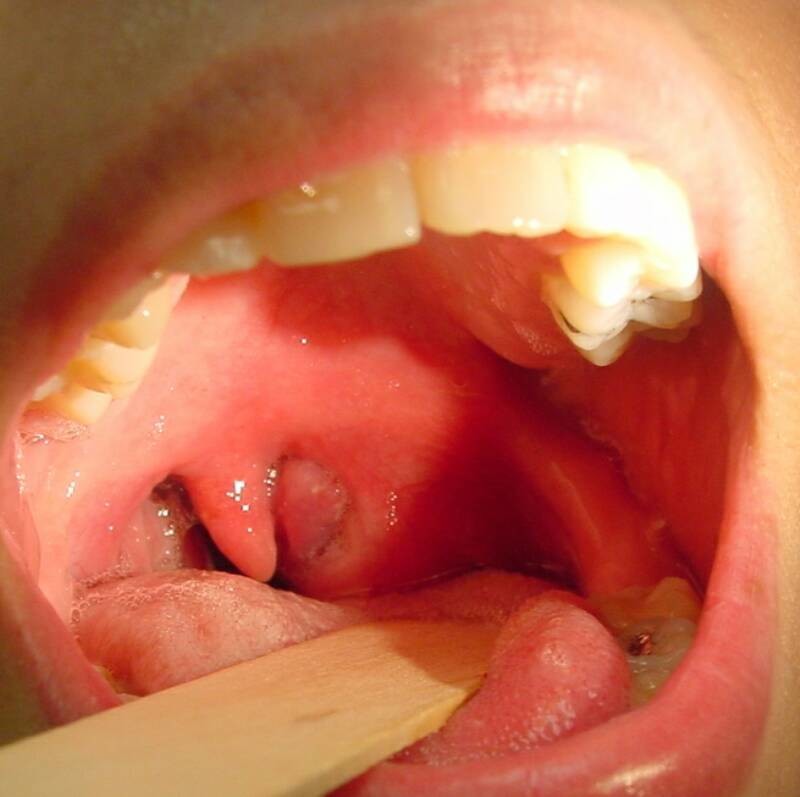

Also known as a peritonsillar abscess, it is a complication of tonsillitis that is left untreated.

The abscess (collection of pus) forms between one of your tonsils and the wall of your throat. This can happen when an infection spreads from an infected tonsil to the surrounding area.